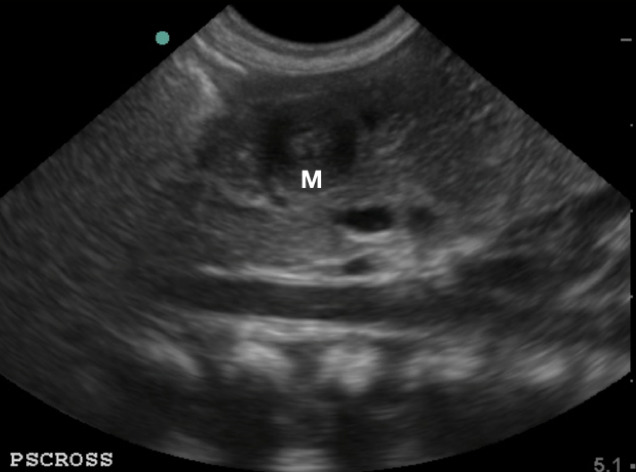

- On the short axis or transverse view, the pylorus has a “target” appearance

- Figure 5. Pylorus in short axis/ transverse view, the “target sign” (M: pylorus muscle)